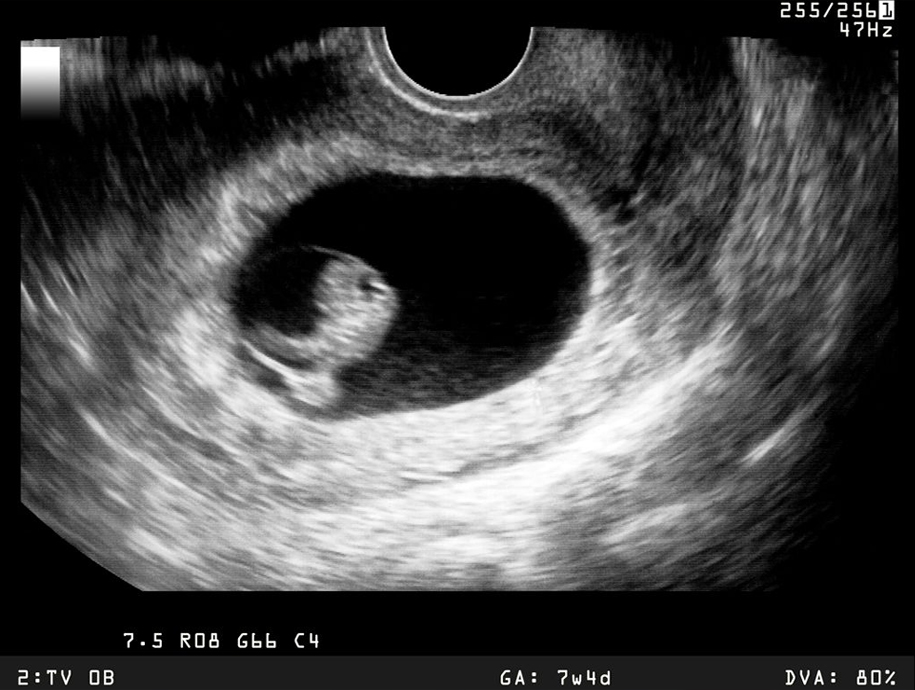

Your First Scan

Your baby’s first milestone with proper medical guidance.

Scan support includes :

- Pregnancy confirmation

- Dating scan guidance

- Early fetal health check

- Doctor consultation

What is the best time for the first pregnancy scan?

The first scan is usually done between 6 to 8 weeks of pregnancy to confirm pregnancy, check fetal heartbeat, and determine the due date.